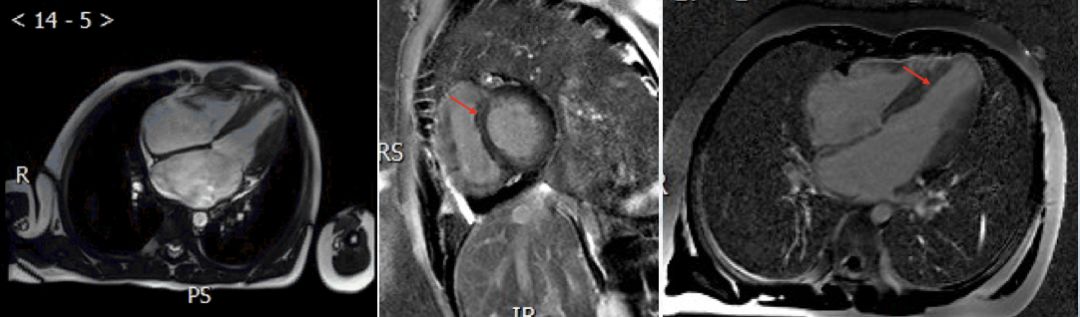

➤ 本病例3例患儿在初始评估后均行CMR检查

CMR:左心室增大,左心室舒张末期内径59.4mm,EF 13.3%

电影MRI:左心室室壁运动减低,收缩功能下降。心包内见少量液性信号影。

心肌延迟强化成像:中央段-心尖段下壁及前壁可见心肌中层线样高信号影

✦ Case 2,幼儿,扩张型心肌病?HF、支原体感染、细小病毒B19感染、流感病毒B感染

复查CMR